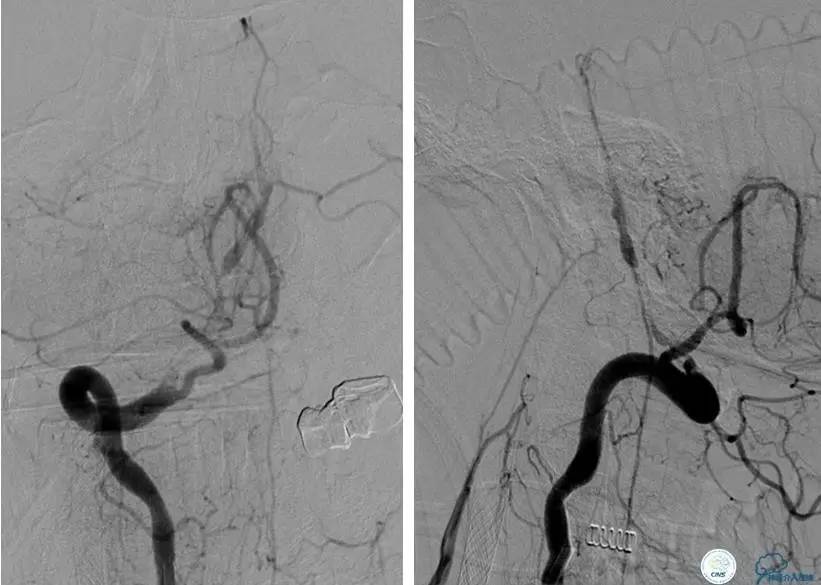

▼DSA示右侧椎动脉发育低下,弥漫性狭窄,可以看到左侧椎动脉反流,因此判断左侧椎动脉V4段CTO。

治疗:

微导丝穿过闭塞段,微导管造影,球扩闭塞段,置入Wingspan支架,血流完全恢复正常。

患者术后2天再次出现卒中发作,药物治疗好转,此后病情稳定。半年后复查DSA,见支架闭塞,侧支循环开放。患者一般情况好,mRS:1分。